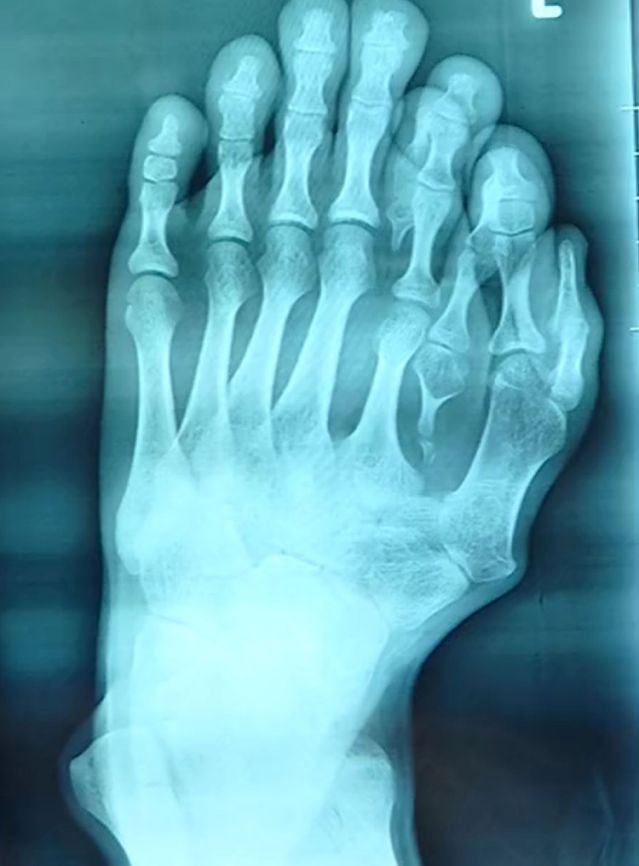

A man named Ajun from Lufeng City in South China’s Guangdong Province was born with nine toes on his left foot and he underwent a rare surgery to remove the extra ones.

He visited a medical professional for advice and his doctor, Wu Xiang, said: “It’s very rare to see such a serious deformity having not been treated in a 21-year-old patient.”

“Other hospitals would’ve just removed his outermost extra toes. That would’ve been the easiest solution, but it wouldn’t look the best.”

“His most natural looking toe is on the outside, so we decided to migrate it inwards to its most ideal position, replacing his fifth digit and creating a new big toe.”